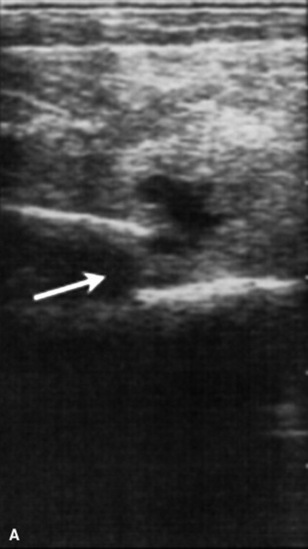

C. immitis is a soil saprophyte that grows in semiarid areas with sandy, alkaline soils.375 Inhaled arthroconidia enlarge to form nonbudding spherules, which incite an inflammatory reaction in the lungs and lymph nodes.375 Horses have weight loss, fever, abdominal pain, and signs of respiratory disease (Fig. 31-26). Localized, recurring nasal granulomas also have been reported.376 Diffuse infections with granulomas in the lungs, liver, kidney, or spleen carry a grave prognosis.375 Przewalskii horses may be more susceptible.377

image image image

Fig. 31-26 A, Coccidiomycosis in a quarter horse mare with severe weight loss after a 3-month period in Arizona and Colorado. Ultrasound image of free (B) pleural fluid and (C) abdominal fluid.

Courtesy Jamie Murphy, Califon, NJ.

C. immitis is difficult to culture, and spherules may not be observed histologically from antemortem lung biopsies. However, serology is very useful to diagnose infection, and decreasing titers are associated with clinical improvement.332,375 Serum antibodies are detected rarely in healthy horses.378 Antifungal agents successful in treatment of infected horses include itraconazole and fluconazole.332,379